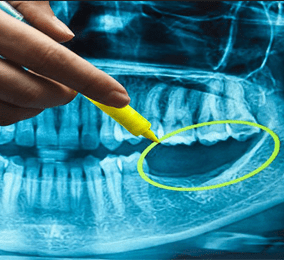

Ảnh chụp X-quang